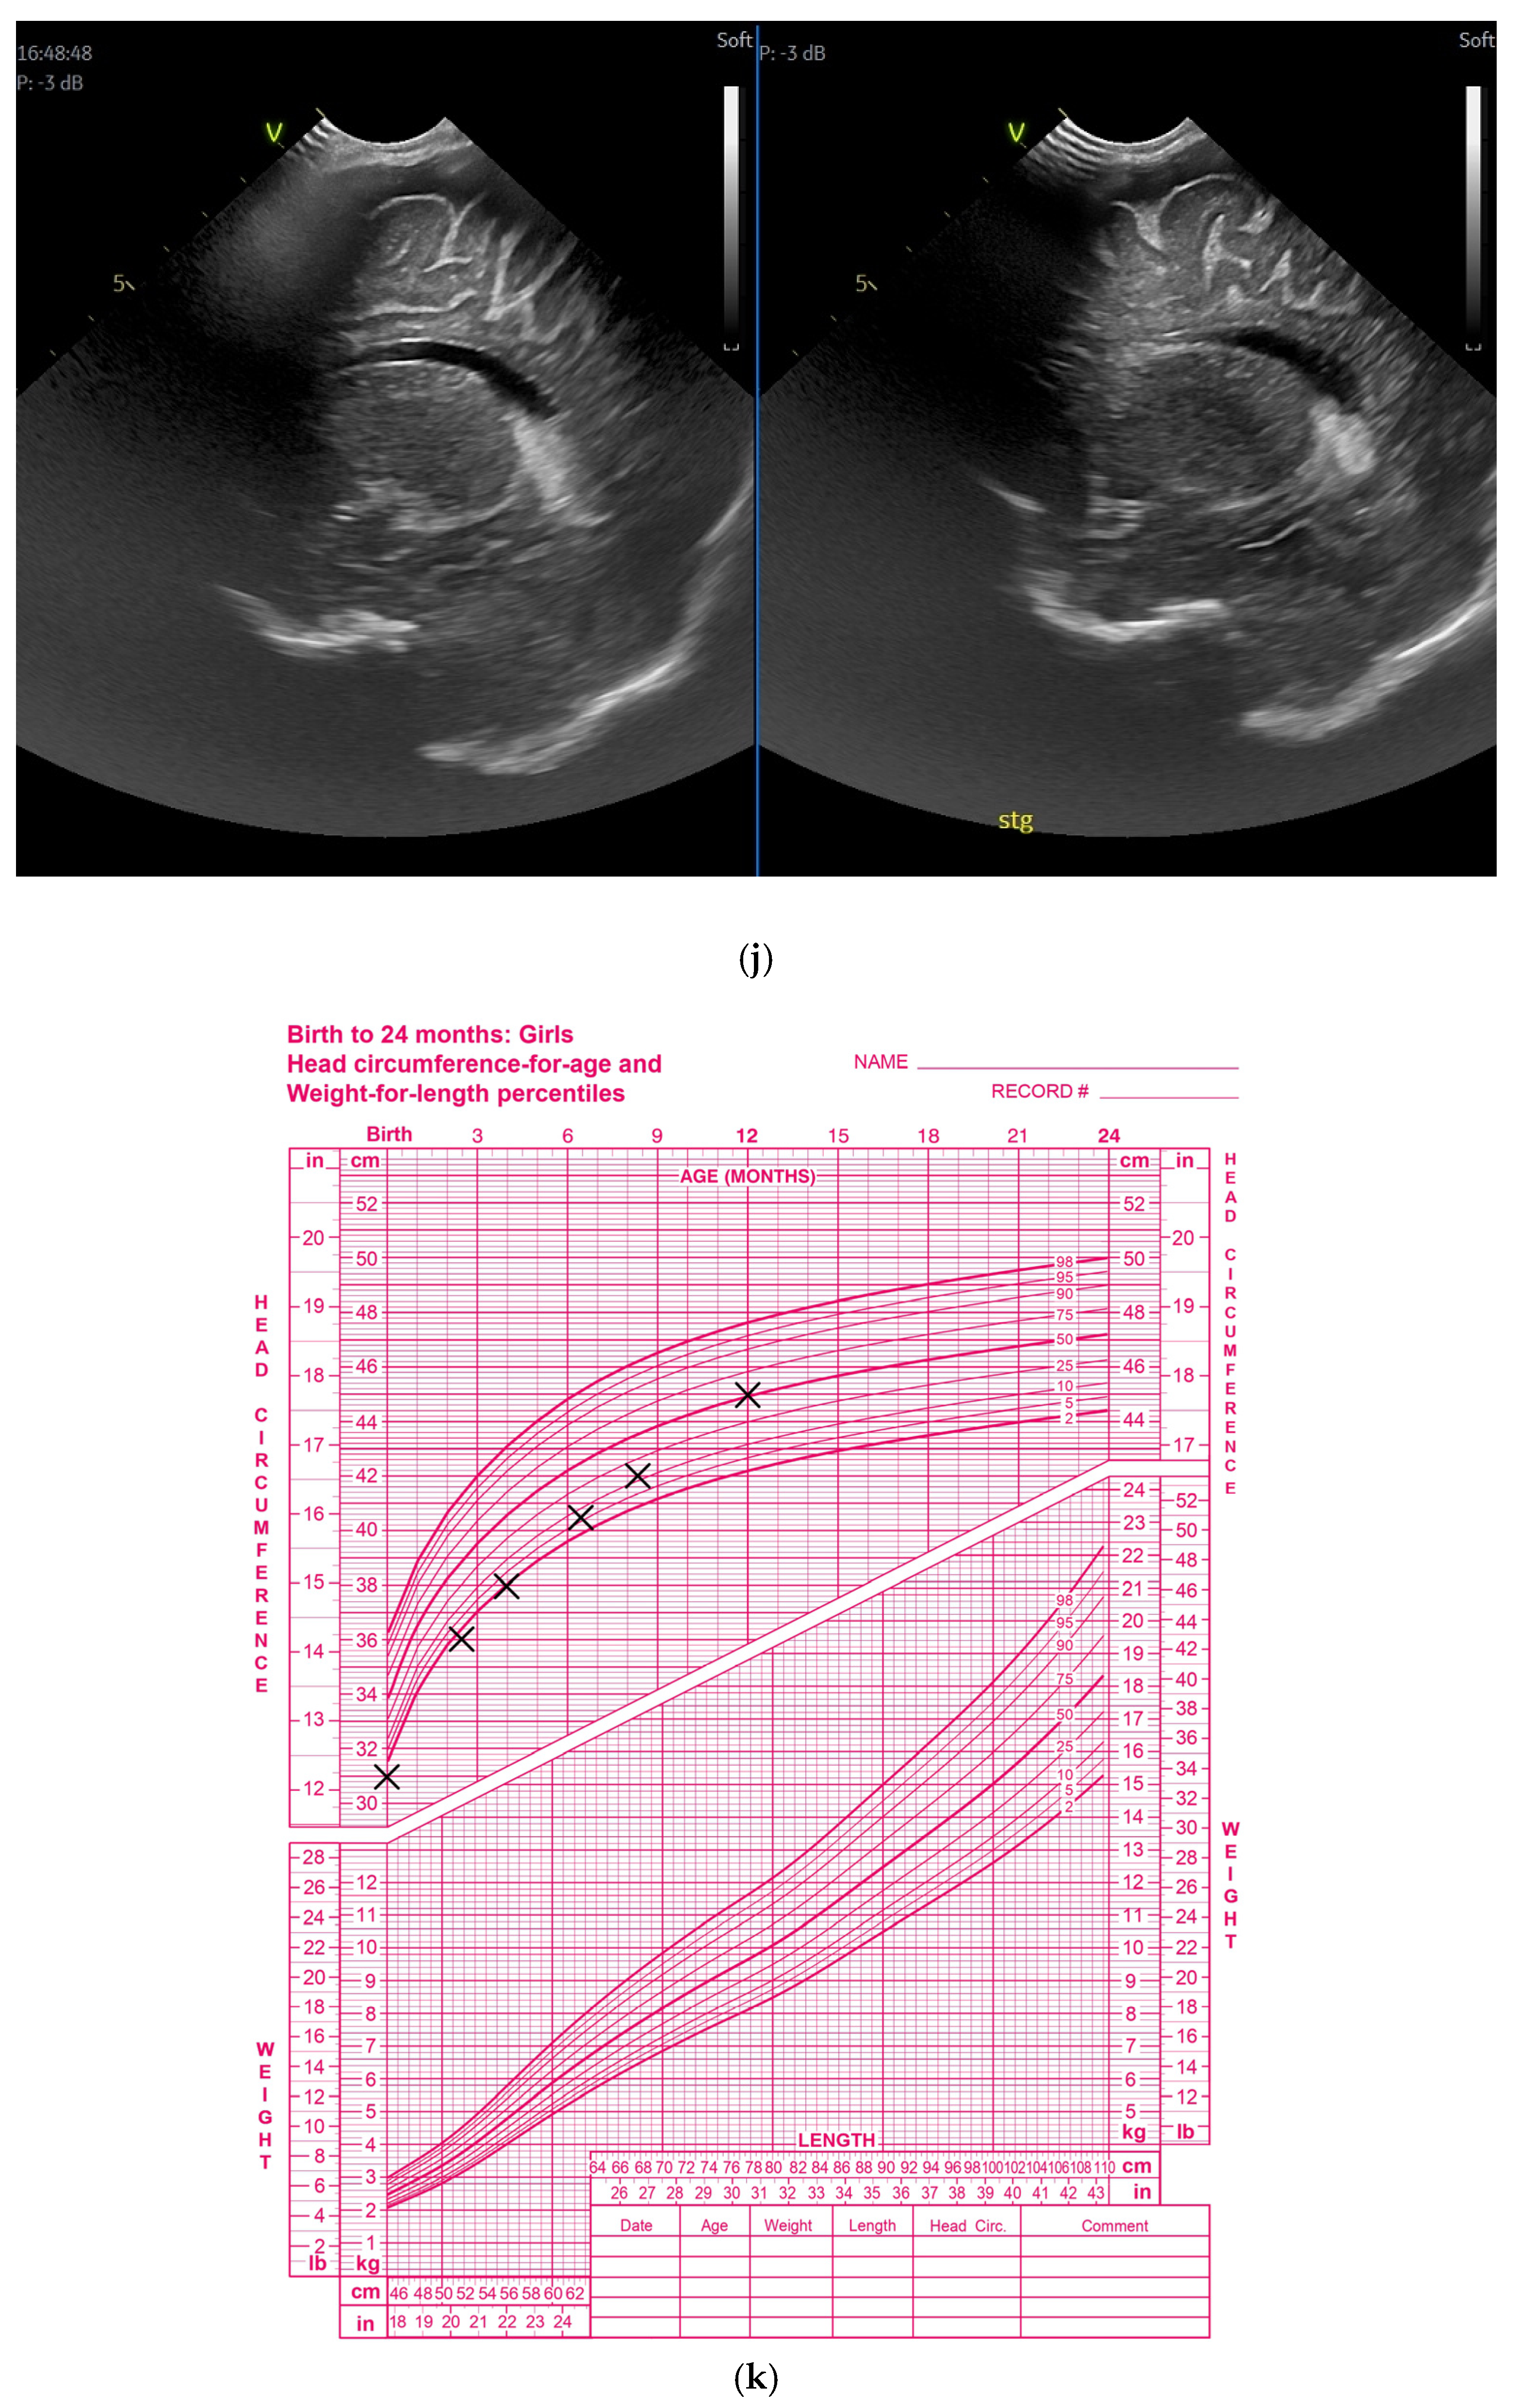

(a) Cranial ultrasound. Coronal view. Enlargement of the lateral ventricles with hyperechoic and third ventricle dilation. D1, D2—Levine index measurement. D3, D4—anterior horn width measurement. D5—third ventricle (personal image collection). (b) Cranial ultrasound. Sagittal view. Up—left ventricle. D1, D2—lateral ventricle measurements and thalamo-occipital horn width. Down—right ventricle. D1, D2—lateral ventricle measurements and thalamo-occipital horn width (personal image collection). (c) Cranial ultrasound. Sagittal view. Up—enlargement of the third and fourth ventricles. Measurements of the ventricles. Down—measurement of the resistive index (RI) performed on the anterior cerebral artery (ACA) using Doppler flow measurements. RI—0.74 (personal image collection). (d) Cranial ultrasound. Transtemporal view. Yellow arrow—enlargement of the Sylvian aqueduct (personal image collection). (e) Cranial ultrasound. Sagittal view. Yellow arrow—arachnoid cyst posterior to the third ventricle (personal image collection). (f) Cranial ultrasound. Coronal view. Lateral ventricles and third ventricle enlargement. D1, D2—Levine index measurement. D3, D6—right lateral ventricle measurement (anterior horn width). D4, D5—left lateral ventricle measurement (anterior horn width) (personal image collection). (g) Cranial ultrasound. Sagittal view. Left—left ventricle. D1—thalamo-occipital distance measurement. Right—right ventricle. D2—thalamo-occipital distance measurement (personal image collection). (h) Cranial ultrasound. Coronal view. Up—orange arrow—third ventricle. Red arrow—fourth ventricles. Yellow arrow—arachnoid cyst. Down—resistive index measured on the anterior cerebral artery. RI—0.79 (personal image collection). (i) Cranial ultrasound. Transversal view. Up—RI precompression value on the middle cerebral artery performed with Doppler examination. RI—68. Down—RI post-compression value on the middle cerebral artery performed with Doppler examination. RI—0.79 (personal image collection). (j) Cranial ultrasound. Up—coronal view. L1, L2—Levine index measurement of the lateral ventricles. Down—sagittal view. L1, L2—measurement of the thalamo-occipital distance (personal image collection). (k) Cranial ultrasound. Sagittal view. L1, L2—measurement of the third ventricle. L3, L4—measurement of the fourth ventricle. L5, L6—measurement of the arachnoid cyst (personal image collection). (l). Head circumference-for-age. “X” symbols represent the measurements performed from birth and follow-up examinations. Head circumference was still under the curve during follow-up examinations (personal image collection) [28].

The CUS examination performed at 48 h after birth showed increases in the diameters of all ventricles. The resistive index presented an increase as well. The bregmatic fontanelle started bulging. The dimensions of the Sylvian aqueduct were not modified (Figure 3f–h).

The CUS examinations performed at four days and seven days after birth showed stabilization regarding the values of the diameters. The pre- and post-compression values of the resistive index of the middle cerebral artery showed a delta-RI of 0.11 (pre—0.68, post—0.79, Figure 3i).

After discharge, at three weeks after birth (follow-up examination), the ventricle measurements showed wider ventricles and the arachnoid cyst was still present (Figure 3j,k).

The next follow-up examination performed a week later showed a delta-RI of 0.12 and an increase in the cranial perimeter (+ one cm since the last follow-up).

At 12 weeks of life (five week corrected age), ventricle dilations were still present. Neurological examinations showed axial and limb hypotonia. The general movement examination showed a poor repertoire with a General Movement Optimality Score (GMOS) of 19. At 18 weeks of life (11 week corrected age), the neurological exam revealed that the infant presented plagiocephaly and could keep eye contact, and during the traction-to-sit maneuver showed hypotonia of the neck muscles. In the prone position, the infant was unable to hold the head up. The passive tone assessment showed the “scarf sign”, with the elbow at the midline bilaterally and a popliteal angle of 90° on the right and 110° on the left. Deep tendon reflexes were present. The general movement (GM) assessment revealed absent fidgety movements, with a Motor Optimality Score (MOS) of 13.